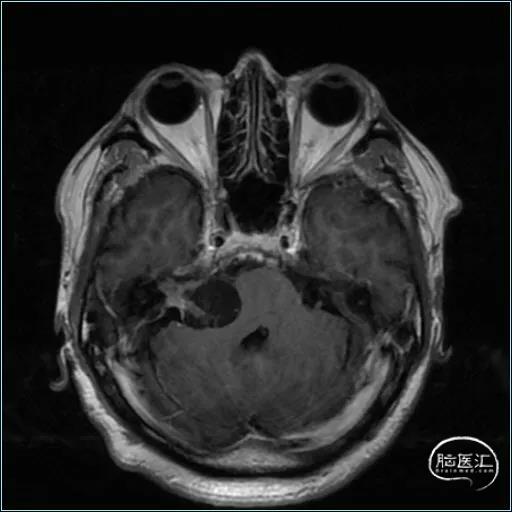

术前影像资料

扩大的内听道

患者:男, 56y,左耳听力下降半年加重3月

肿瘤最大径约3.6cm